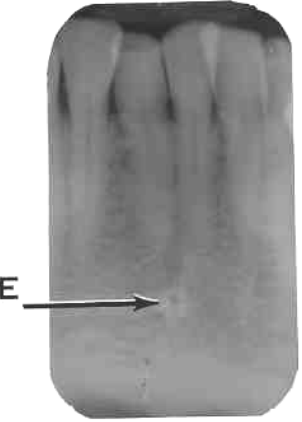

11. Which option is indicated by arrow E?

13. Arrow E showing which anatomical structure?

14. What is showing by E?